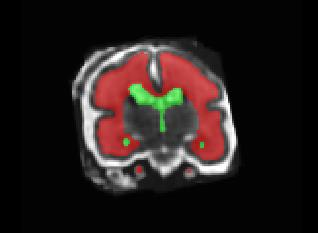

Limiting failures of machine learning systems is of paramount importance for safety-critical applications. In order to improve the robustness of machine learning systems, Distributionally Robust Optimization (DRO) has been proposed as a generalization of Empirical Risk Minimization (ERM). However, its use in deep learning has been severely restricted due to the relative inefficiency of the optimizers available for DRO in comparison to the wide-spread variants of Stochastic Gradient Descent (SGD) optimizers for ERM. We propose SGD with hardness weighted sampling, a principled and efficient optimization method for DRO in machine learning that is particularly suited in the context of deep learning. Similar to a hard example mining strategy in practice, the proposed algorithm is straightforward to implement and computationally as efficient as SGD-based optimizers used for deep learning, requiring minimal overhead computation. In contrast to typical ad hoc hard mining approaches, we prove the convergence of our DRO algorithm for over-parameterized deep learning networks with ReLU activation and a finite number of layers and parameters. Our experiments on fetal brain 3D MRI segmentation and brain tumor segmentation in MRI demonstrate the feasibility and the usefulness of our approach. Using our hardness weighted sampling for training a state-of-the-art deep learning pipeline leads to improved robustness to anatomical variabilities in automatic fetal brain 3D MRI segmentation using deep learning and to improved robustness to the image protocol variations in brain tumor segmentation. Our code is available at https://github.com/LucasFidon/HardnessWeightedSampler.